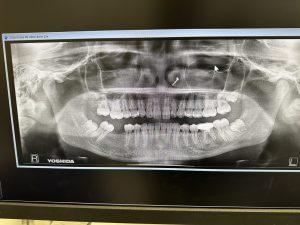

➁

13年振りの来院、力による骨破壊、コンプレッション

syndこれは抜歯しかない

私がやれば、ば良くなります!

インプラントやるかは不明だが、提案、自己投資次第

健康寿命からの逆算